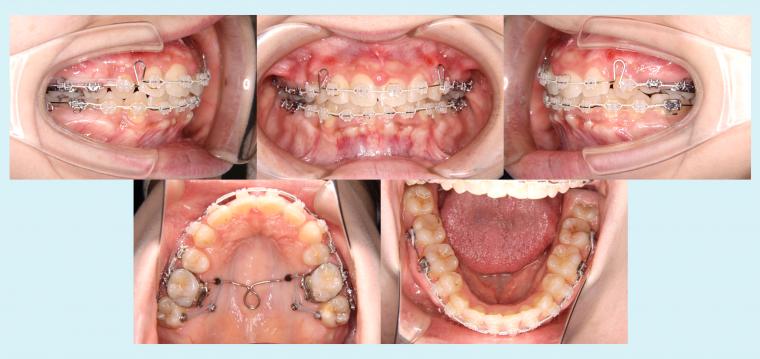

#51 矯正用インプラントアンカーを用いてオートローテーションを図った症例